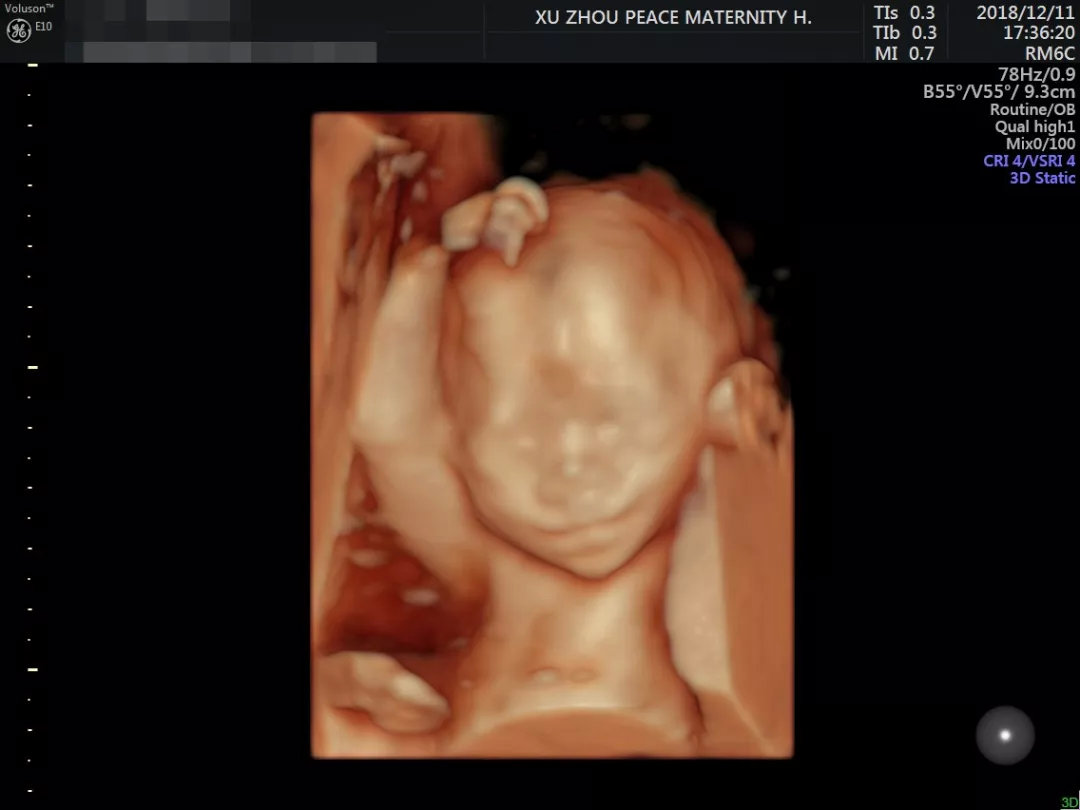

四维彩超作为孕期的重要产前筛查手段,可以提前查出宝宝是否有先天缺陷,便于及时采取干预措施。准妈妈们也可以借着这个机会与宝宝来一场“超时空的相见”。

对于准妈妈而言,四维彩超的超高清成像,一方面能够更直观立体地显示宝宝身体器官的结构和状态,并动态、实时地观察胎宝宝的发育状况,更精准地排查异常情况,保障宝宝健康成长。

另一方面也能让准妈妈更加清晰地看见宝宝的模样,贴心满足妈咪们提前与宝贝“见面”的心愿~

徐州和平妇产医院GE-E10四维彩超拥有超高清画质,质量更可靠,收获了不少准妈妈的认可。产检期间,为了避免长时间的等待,准妈妈们可以提前预约,尽量减少与外界不必要的接触哦。